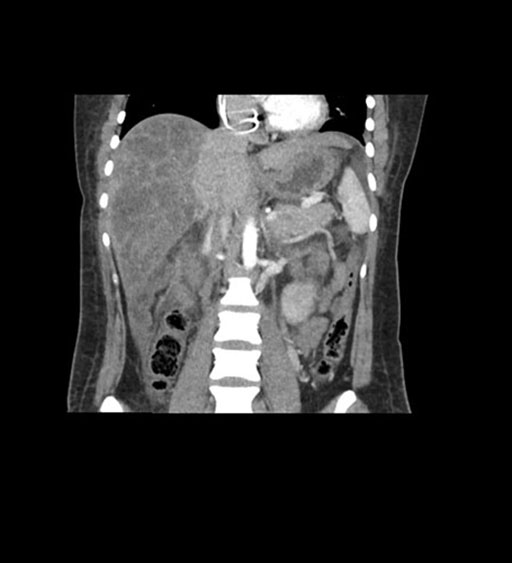

Coronal Arterial

Imaging analysis

Based on initial findings, which issue(s) would you be most concerned about?